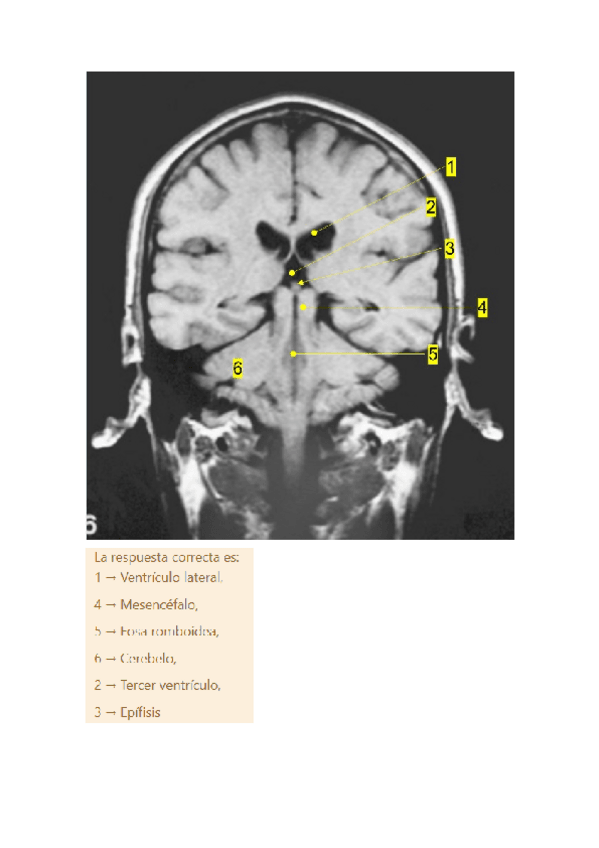

Si sabes rotular las estructuras de estas imágenes tienes el práctico hecho.